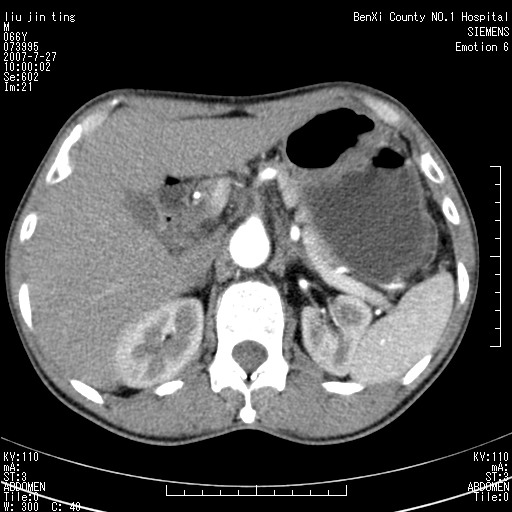

腹痛,背痛,无恶心呕吐,不黄,彩超示胰腺钩癌,ct扫描病灶平扫30-40hu,增强后动脉期40--60hu,静脉期50-68hu,真的是钩突上的么?您要试一试么?

动脉期

静脉期

沿着肠系膜上动脉呈匍匐性生长的软组织肿块,形态不规则,包绕肠系膜上动脉,呈明显强化,考虑来源于肠系膜的恶性肿瘤

沿着肠系膜上动脉呈匍匐性生长的软组织肿块,形态不规则,包绕肠系膜上动脉,呈轻-中度强化,考虑来源于肠系膜的恶性肿瘤。

钩突是正常的,只见腹膜后淋巴结的肿大,考虑淋巴瘤或转移可能。

支持!恶性纤维组织细胞瘤可能,与淋巴瘤及淋巴结转移鉴别(腹主动脉周围清晰,其他部位亦未见明显肿大淋巴结)。